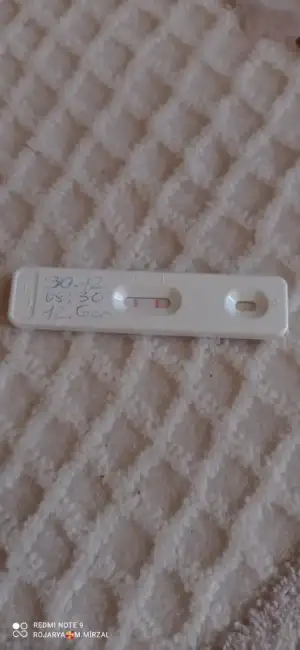

Cnm nasil yaptin anlatsan erkek bebek icin esin fala kan verdimi cin takvimi tuttumjZor oluyormuş evet bu ay takip yapıyorum sadece önümüzdeki ay nasipse hem doktor kontrolü hemde testle deneme yapacağım inşaallah